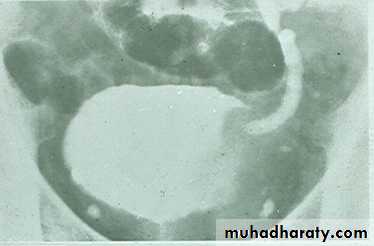

*Calcification is very common and important diagnostic findings. Very common in bladder ,less frequent in lower ureters ,but in advanced case involve the whole length of ureter .

*The appearance depends on degree of fullness of bladder ; thin linear opacity outlining bladder wall.

Empty bladder shows crowded linear opacities with calcified plaques.

Urinary Schistomiasis

• IVU: Early stage –cobble stone Later filling defects due to graneulomatos papilloma Carcinoma is important complication Ureters : dilated and tortuousIn early stage hydroureter and hydronephrosis + refluxSPACE OCCUPING LESION